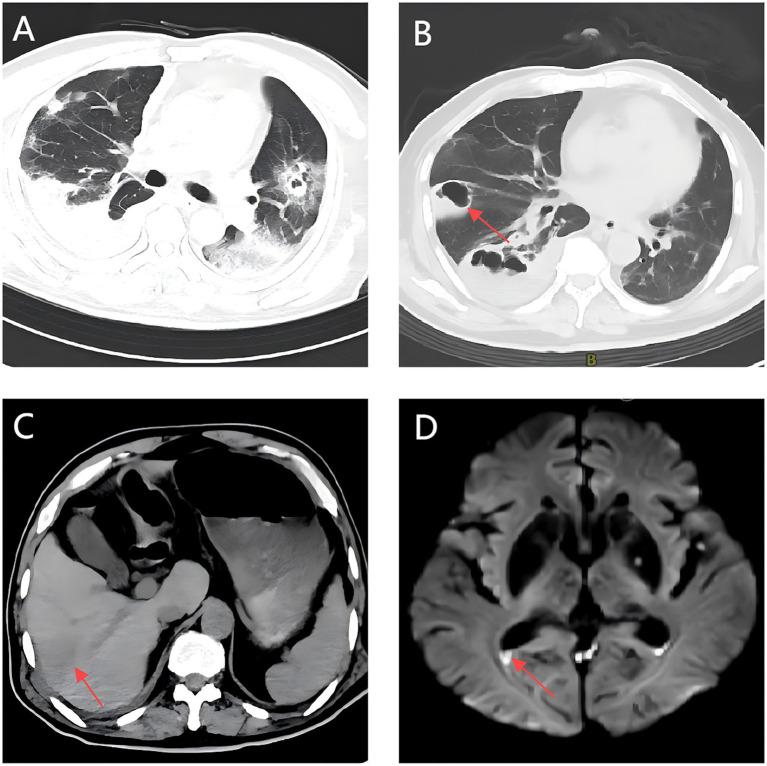

We describe a 70-year-old diabetic male with recurrent ILAS who developed sequential multi-organ infections, including urinary tract infection, bacteremia, lung abscess, and brain abscess. Initial isolates were identified as carbapenem-susceptible; however, under prolonged antimicrobial pressure, they were transformed into CR-hvKp carrying the KPC gene. Treatment escalated from meropenem to ceftazidime-avibactam plus tigecycline, resulting in clinical improvement and discharge after 48 days.